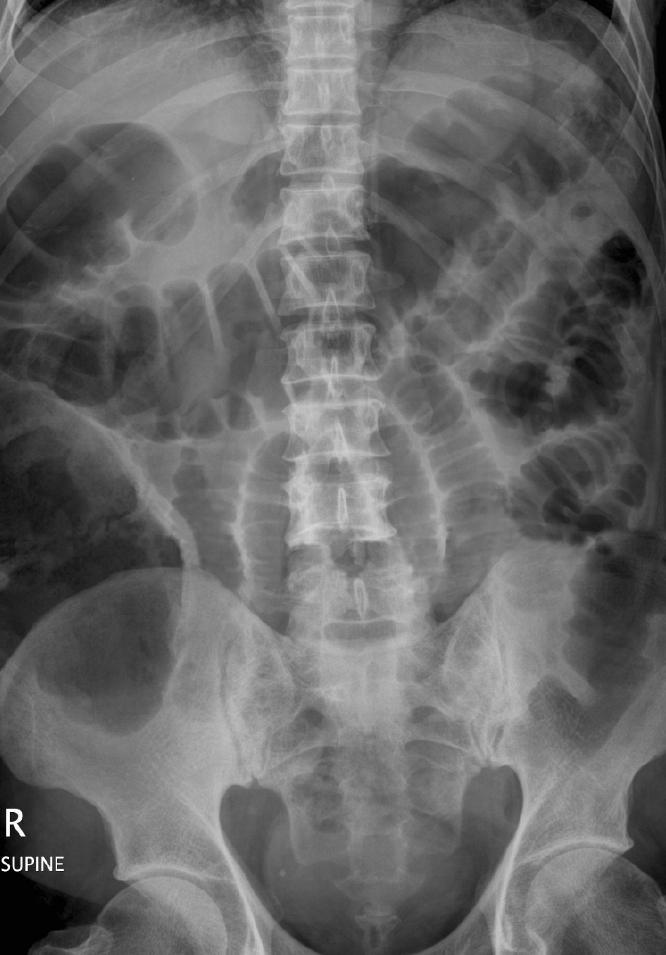

Pneumoperitoneum